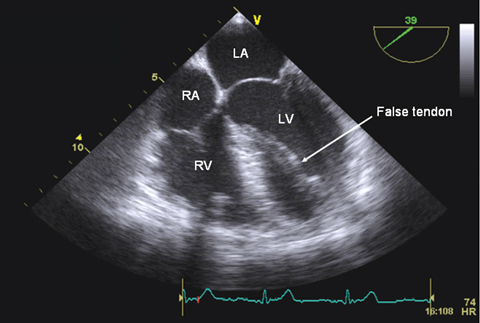

A 45-year-old man presented with frequent palpitations. Clinical examination and electrocardiogram were unremarkable. Transthoracic echocardiography suggested asymmetrical septal hypertrophy, although the acoustic windows were poor. Transoesophageal echocardiography revealed a broad false tendon within the left ventricle, extending from the basal septum to the apical lateral wall (Figure). Holter monitoring showed frequent premature ventricular complexes, indicating right bundle branch block morphology.

The incidence of false tendons — fibromuscular intracavitary bands anatomically distinct from the valvular cusps — is 0.4% to 3.0%.1 They may be associated with malignant ventricular arrhythmias, which should be excluded before making a diagnosis of benign premature ventricular complexes in a healthy patient.1